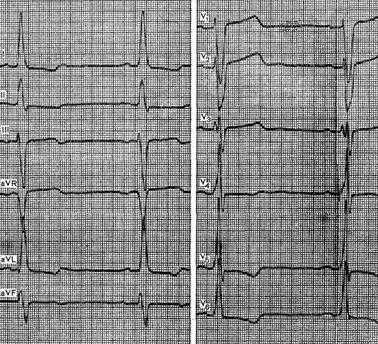

Рис. 2.15. Диагноз «хронический пиелонефрит со сниженной концентрационной функцией почек, сохранной азотовыделительной функцией почек. Артериальная гипертензия, риск высокий». В течение 9 лет повышенное артериальное давление с подъемами до 220/130 мм рт.ст. По данным суточного мониторирования артериального давления отмечается повышение систолического и диастолического артериального давления (среднее систолическое артериальное давление днем - 149 мм рт.ст., среднее диастолическое артериальное давление днем - 105 мм рт.ст.). Эхокардиография: признаки увеличения левого предсердия (левое предсердие - 3,0 см, 4,6x4,8 см апикально), полость левого желудочка расширена (конечно-диастолический размер - 5,25 см, конечно-систолический размер - 3,3 см). Сократимость удовлетворительная: фракция выброса - более 60%. Утолщение задней стенки левого желудочка и межжелудочковой перегородки (толщина задней стенки левого желудочка - 1,48 см, толщина межжелудочковой перегородки - 1,48 см). Электрокардиография: синусовая брадикардия, средняя частота сердечных сокращений - 57. Атриовентрикулярная блокада I степени. Отклонение электрической оси влево. Полугоризонтальная позиция сердца. Изменения предсердного компонента с чертами увеличения левого предсердия. Признаки изменения миокарда вследствие гипертрофии левого желудочка: высокие зубцы r в левых грудных отведениях, глубокие зубцы s в правых грудных отведениях

При ГЛЖ изменения конечной части желудочкового комплекса выявляются в левых грудных отведениях (V5 , V6 ) и в отведениях I, II, aVL (при горизонтальной позиции) либо в II, III, aVF, V5 -V6 (при вертикальной позиции). Это левожелудочковый тип напряжения (см. рис. 2.15).

Сочетание признаков левожелудочкового напряжения с повышенным вольтажом желудочкового комплекса относят к систолической перегрузке. Повышенный вольтаж qrs на ЭКГ без изменений конечной части желудочкового комплекса считается признаком диастолической перегрузки. Количественные критерии ГЛЖ: